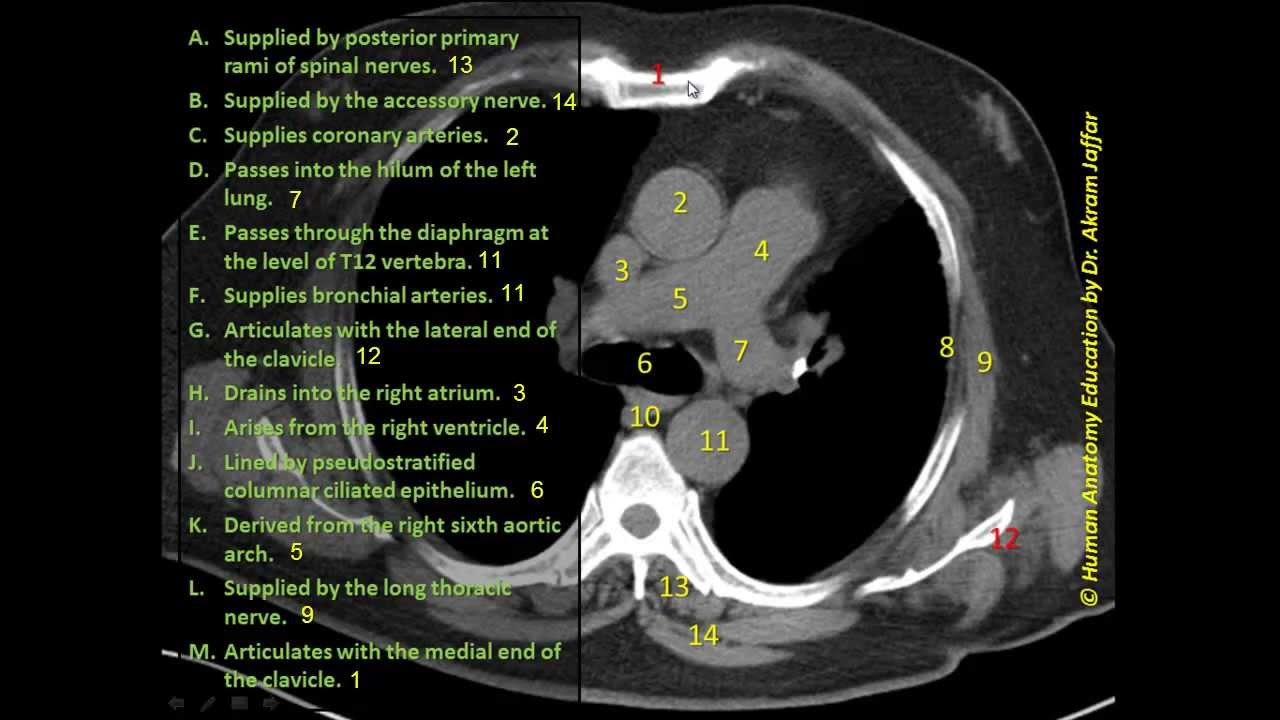

Labeled Chest Ct Scan Anatomy My Xxx Hot Girl As a result of ever increasing unsanctioned scraping by bots, we have instituted a challenge designed to keep them out, and make sure real users get the best experience possible. if you're not a bot, you shouldn't see this error. if it persists, please contact [email protected] and we'll help to unblock you. Typically, cardiac ct axial examinations are specifically tailored to image the heart, and therefore the imaging volume is restricted to only a portion of the thorax. often the examination begins just below the carina, as this first plate shows. These axes are also used in cardiac ct mr and must be reconstructed in order to assess the heart properly. axial slices, such as those imaged on the left, are useful for a global assessment of the morphology of the heart and its relation to the pericardium. This document describes the normal cardiac anatomy as seen on axial ct images at different levels through the heart. it provides labels and descriptions for key structures visible on each image slice, such as the pulmonary veins and arteries, coronary arteries, atrial walls and septa.

Heart Ct Scan Diagram Quizlet These axes are also used in cardiac ct mr and must be reconstructed in order to assess the heart properly. axial slices, such as those imaged on the left, are useful for a global assessment of the morphology of the heart and its relation to the pericardium. This document describes the normal cardiac anatomy as seen on axial ct images at different levels through the heart. it provides labels and descriptions for key structures visible on each image slice, such as the pulmonary veins and arteries, coronary arteries, atrial walls and septa. Cardiac ct scans can help find out how bad coronary artery disease is, guide treatment choices, and see if interventions are needed. looking at these four key images, doctors can fully understand the heart’s anatomy. Segmental models for describing coronary artery anatomy are presented. metrics for normal coronary artery diameter and left atrial area are provided. common cardiac imaging planes and structures like the left ventricle and valves are also depicted. download as a pptx, pdf or view online for free. We have established a large scale database of cardiac imaging examinations and associated models and derived measurements in order to develop a shareable, web accessible, structural and functional atlas of the normal and pathological heart for clinical, research and educational purposes. Manually annotated visualization of a ct scan of the human heart. a hybrid label layout is used, while the internal labels are represented as 3d labels providing additional shape cues.